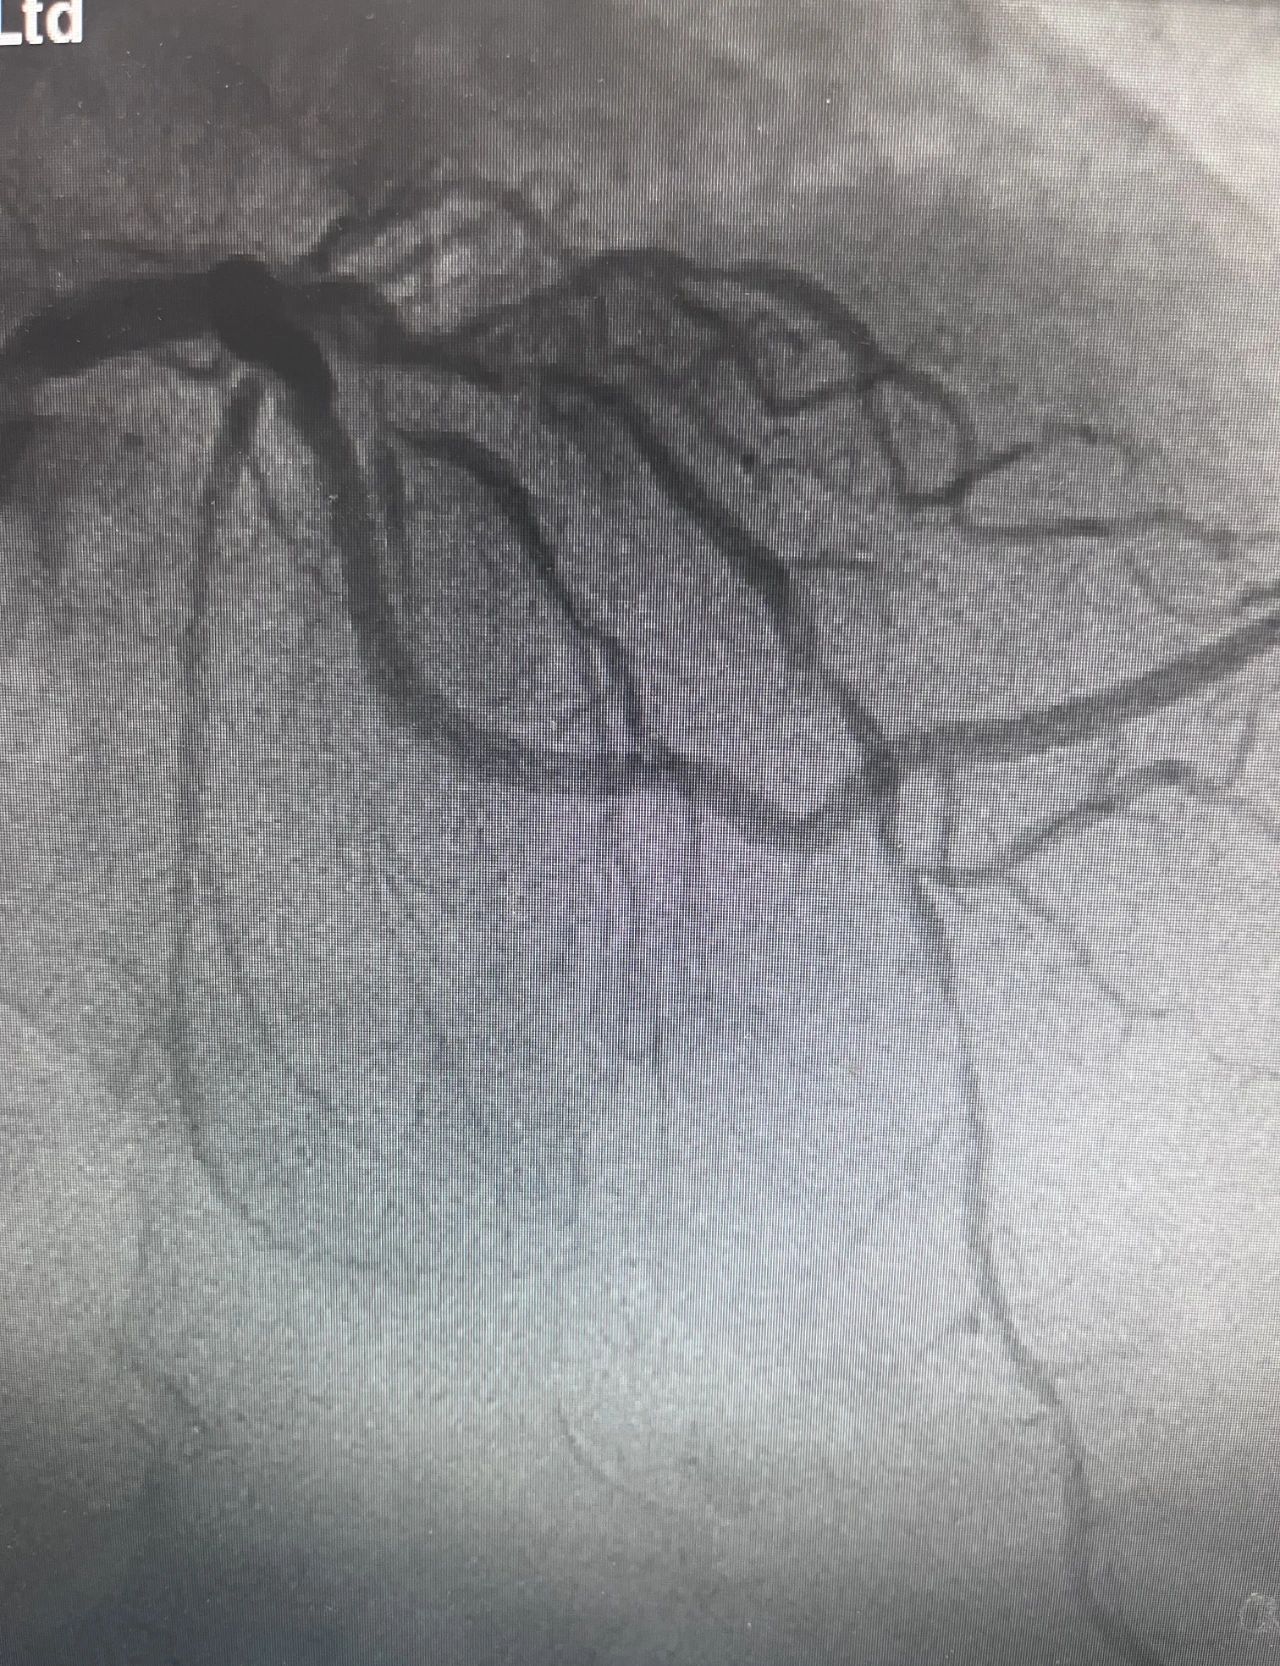

59岁的刘先生因间断性胸闷、胸痛1周到蜜桃视频-麻豆蜜桃 心内二科住院治疗。入院完善相关检查,诊断为冠心病、不稳定性心绞痛、陈旧性心肌梗死 ,冠脉造影检查提示前降支近段及中段均有弥漫性钙化伴重度狭窄病变,最重约99%。

前降支术前病变